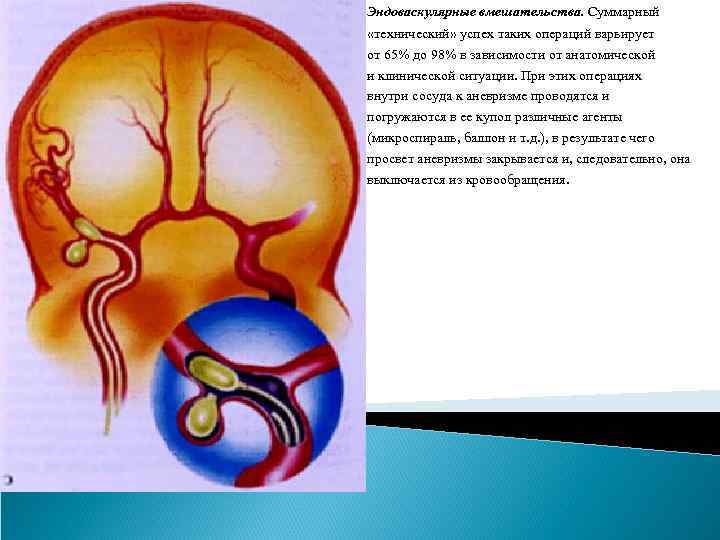

Методы лечения аневризм сосудов головного мозга. Определение аневризмы сосудов мозга является прямым показанием к проведению лечения, которое является исключительно хирургическим: - клипирование аневризмы (открытые вмешательства), - эндоваскулярное вмешательство Клипирование аневризмы. Целью внутричерепного (открытого) вмешательства на аневризме является выключение ее из кровотока при сохранении проходимости несущего и окружающих сосудов, удаление крови из субарахноидального пространства. Эти операции относятся к ряду наиболее сложных операций в нейрохирургии. Операция должна быть минимально травматична, что обеспечивается выполнением оптимальных хирургических доступов, микрохирургической техники и одномоментным клипированием шейки аневризмы. Для выполнения операции используется операционный микроскоп, специальный микрохирургический инструмент. При открытом вмешательстве, проведенных в условиях специализированных отделений крупных центров, летальность после операции в остром периоде кровоизлияния составляет 8 -16%, а в хроническом периоде кровоизлияния (через 1 месяц после него) – не более 2 -3%.

Эндоваскулярные вмешательства. Суммарный «технический» успех таких операций варьирует от 65% до 98% в зависимости от анатомической и клинической ситуации. При этих операциях внутри сосуда к аневризме проводятся и погружаются в ее купол различные агенты (микроспираль, баллон и т. д. ), в результате чего просвет аневризмы закрывается и, следовательно, она выключается из кровообращения.